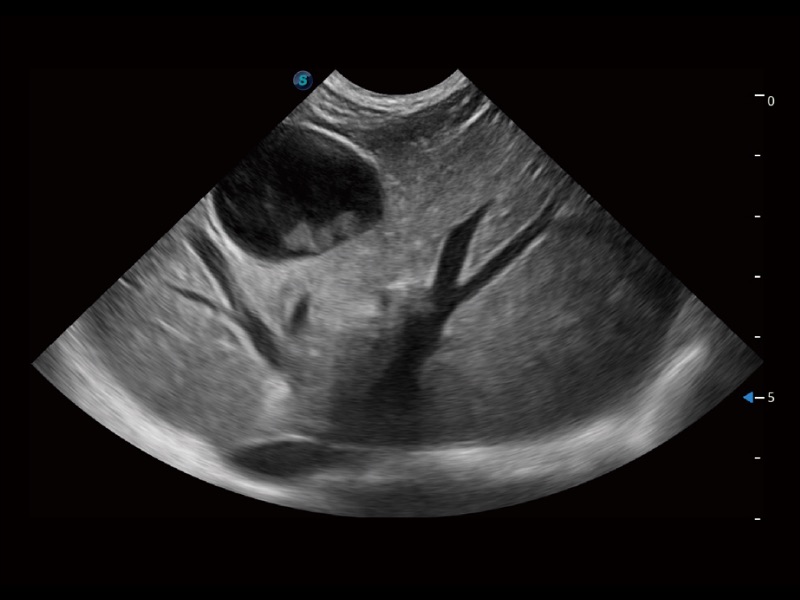

通过色彩血流和实时宽景相结合,可观察到完整的静脉或动脉的血流,方便医生检查。实时扫查过程中,如有任何操作失误也可以很容易地进行回扫擦除,而不会中断扫查。

一键自动识别膀胱壁及自动测量膀胱容积,不受膀胱形状和大小的限制,帮助医生快速精准获得测量的数据。